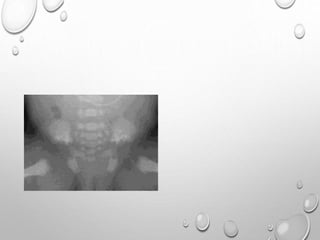

PELVIS

SMALL

ILIA ARE SHORT CAUDALLY

HORIZONTALLY PLACED ACETABULLA , THICKENED Y CARTILAGE

• 1. DYSPLASTIC OR SQUARE

ILIAC BONES

2. NARROW SACRO-SCIATIC

NOTCHES

3. FLAT BILATERAL

ACETABULAR ROOFS

4. SHORT BOTH FEMORAL

NECKS

5. CHAMPAGNE GLASS-

SHAPED PELVIC CAVITY

PELVIS – MULTIPLE DENSE CURVED LINES PARALLELING THE ILIAC

CREST